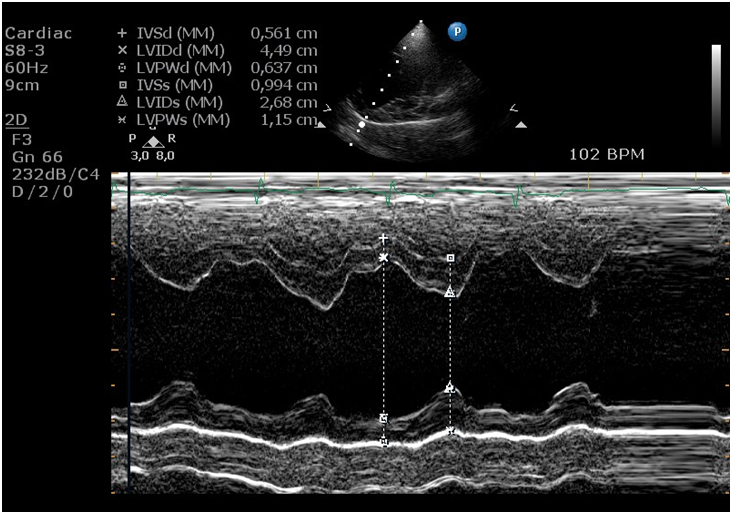

Weil nur mittels einer Herzultraschalluntersuchung DCM definitiv diagnostiziert werden kann, sollte auch diese Untersuchung Pflicht sein für die Zucht.

Goldstandard 24 Stunden EKG

Sas 24 Stunden EKG zusammen mit der Herzultraschalluntersuchung ist der Goldstandard des

DCM- Screenings beim Dobermann.